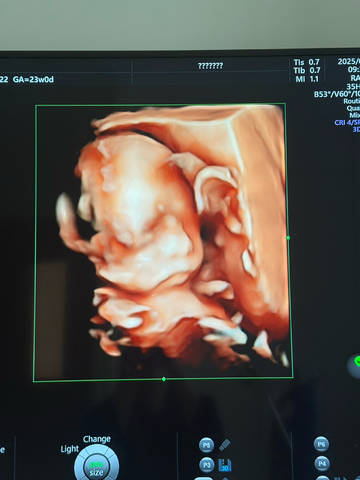

女鹅梦破碎,四维已过,是个臭小子

四维确认是小子,有点小遗憾呢~